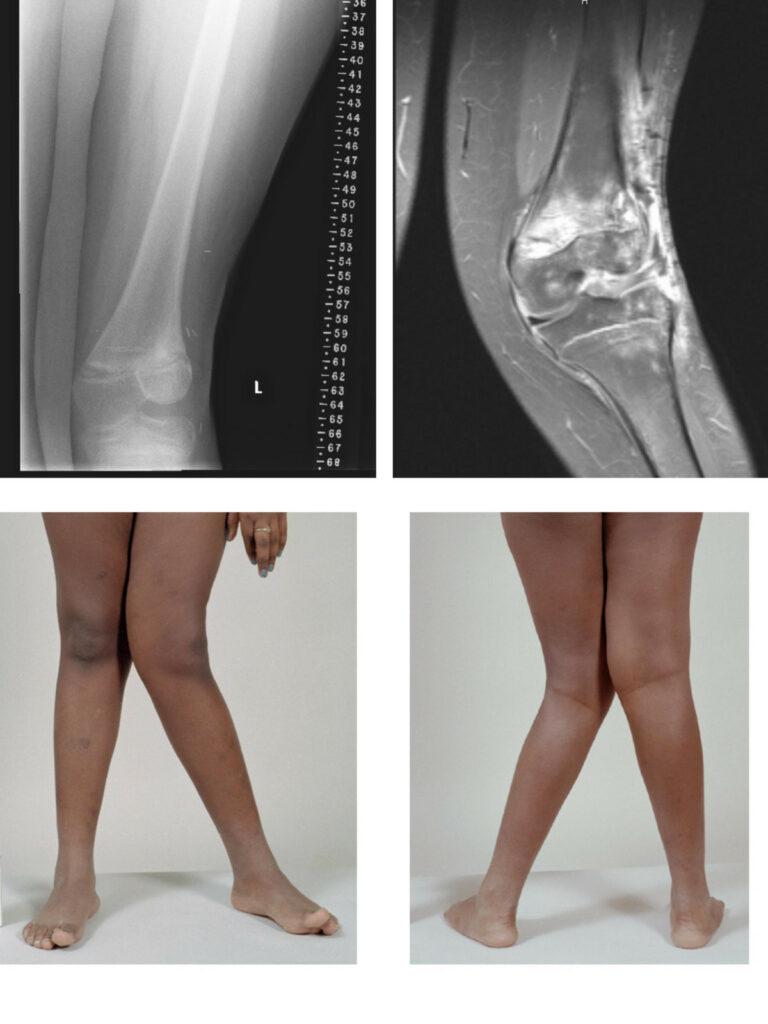

Knee valgus, when the knee rotates inward, might look like a random body quirk.

Knee valgus is a total body action. A strategy your body uses when it reaches a critical threshold.

But what happens if IR demands exceed what the body is capable of producing? Then, many bones move together as a unit. This can create focal loading on certain areas and contribute to knee valgus.

When the pelvis tips forward, it’s like a domino effect. Your femur rotates into IR, your tibia goes the other way, then BOOM. Knee valgus.

Here, the IR occurs locally at the knee. This creates a twist within the femur.